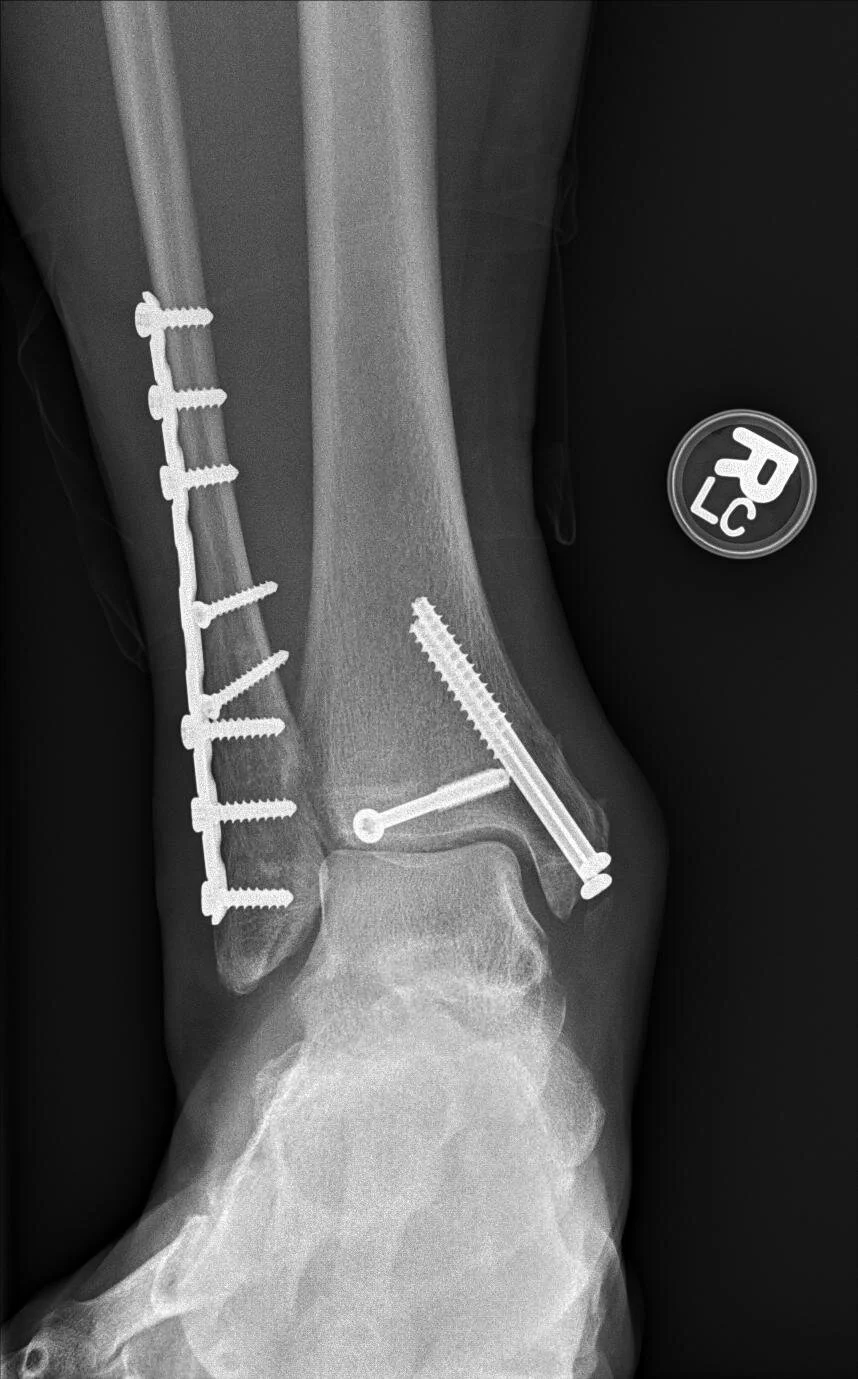

Surgery for fractures involves making an incision in the skin, putting the bones back into place, and keeping the bones in place using metal devices like plates and screws. In most cases, the metal can stay inside forever without issue.

Trimalleolar ankle fracture

Bimalleolar ankle fracture

Lateral malleolar ankle fracture with syndesmotic rupture